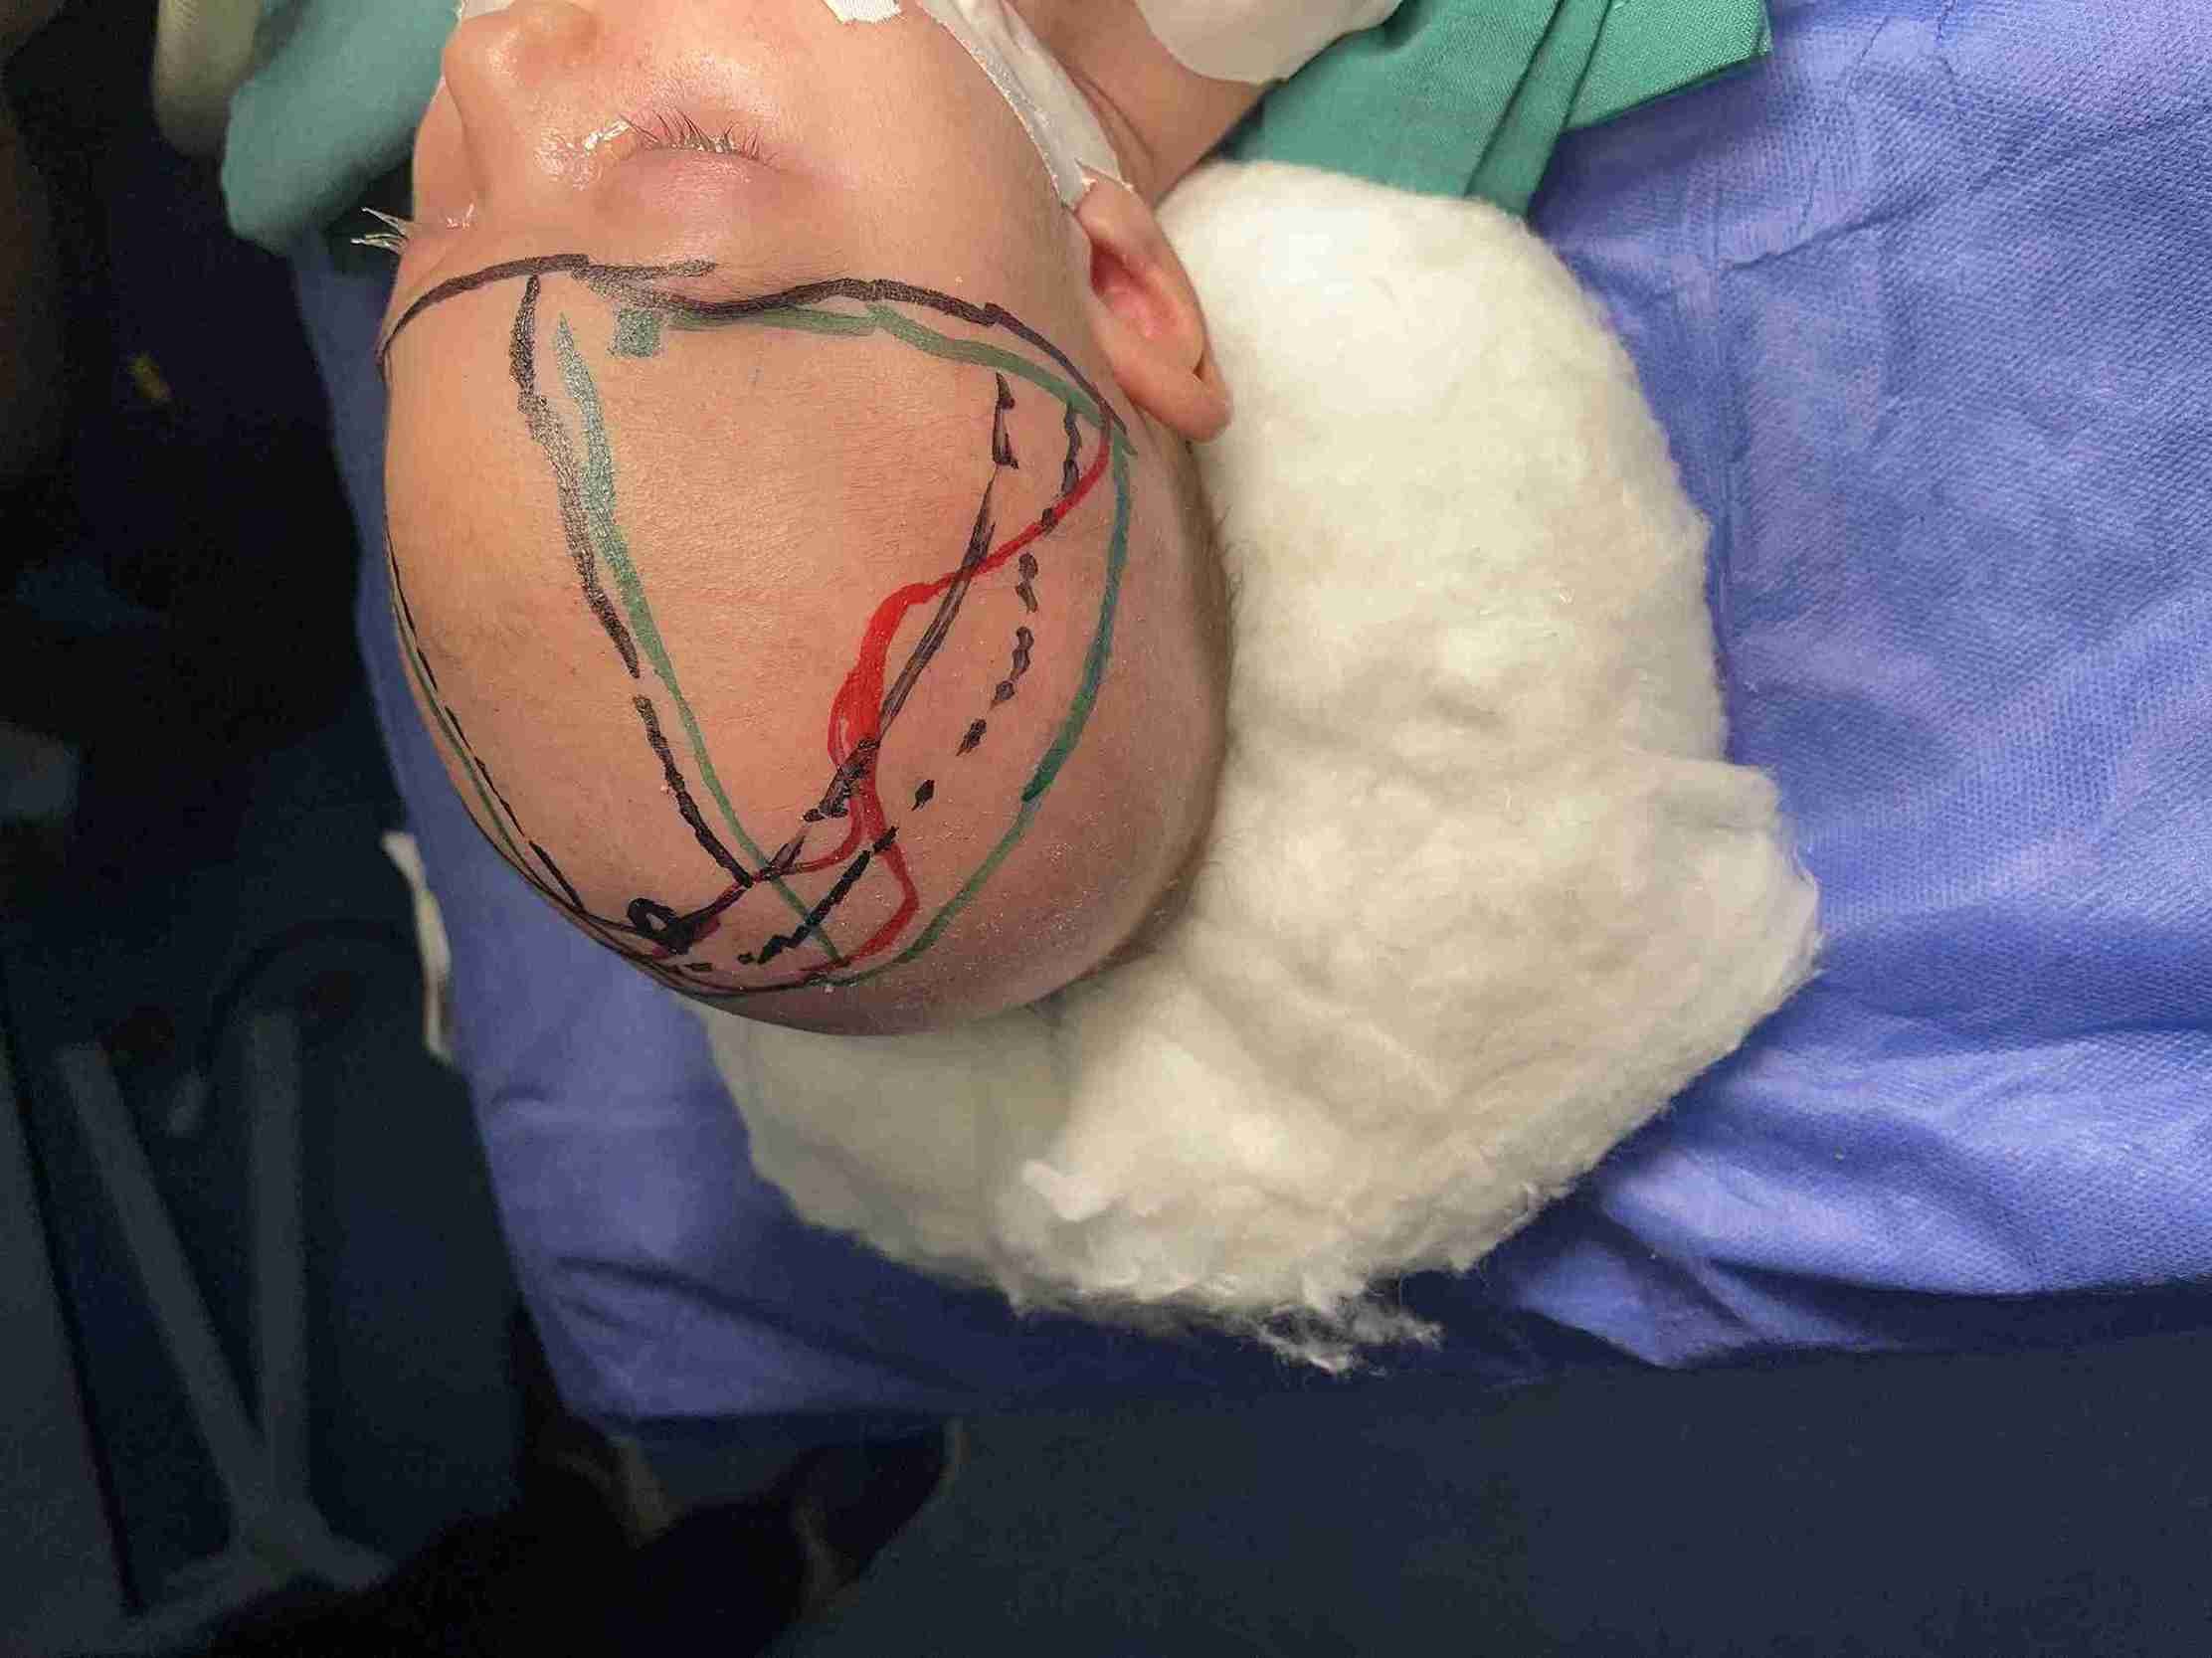

تم إجراء جراحة تقويم ناجحة لطفل يبلغ من العمر شهرين كان يعاني من حالة تعرف باسم "الرأس المثلث". هذا النوع من التشوهات الجمجمية يؤدي إلى ظهور الرأس بشكل مثلثي مع وجود نتوء بارز في الجبهة. الهدف من الجراحة كان تصحيح شكل الجمجمة لضمان النمو الطبيعي للدماغ وحماية الطفل من المشاكل المستقبلية.

• إعادة تشكيل عظام الجمجمة لتصحيح الشكل المثلثي

• إزالة النتوء العظمي البارز في الجبهة

• استخدام أحدث التقنيات الجراحية الآمنة للأطفال الرضع

• تخطيط دقيق مسبق باستخدام التصوير ثلاثي الأبعاد